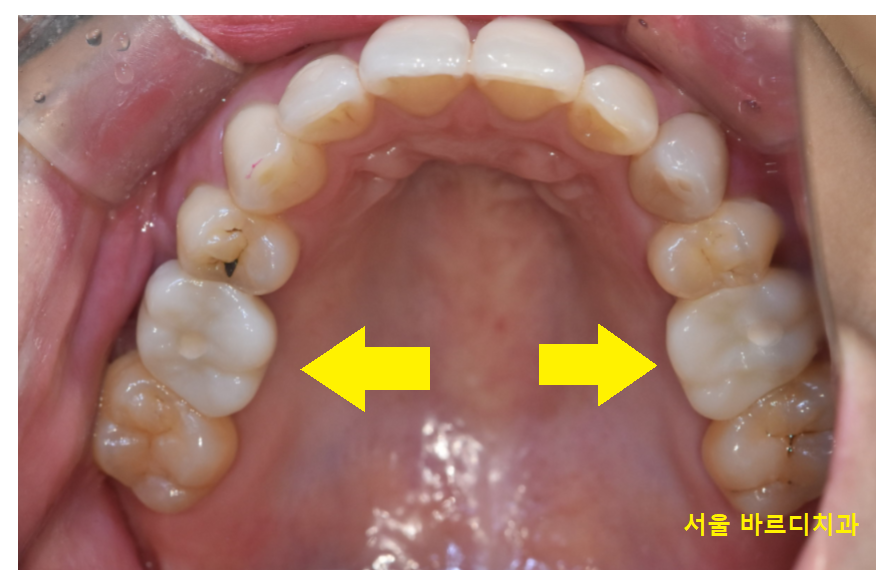

임플란트 양쪽 동시에 해야하는 경우

잇몸 절개가 동시에 진행해야해서

많이들 불편해하시지만

풍산동 치과는 90% 이상을

무절개 임플란트를 시행합니다.

불필요한 잇몸 절개 꼬맴이 없어서

양쪽 임플란트 동시에 수술해도

일상생활, 일상 문제 없습니다!